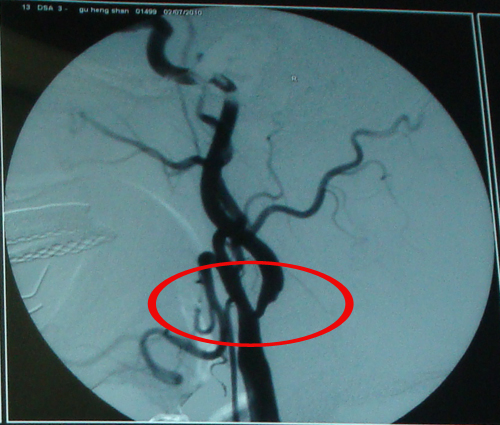

DSA示:右侧颈内动脉起始端管腔重度狭窄

该患者为老年男性,颈内动脉重度狭窄,伴间断性头晕、头痛20年,高血压病史8年,为脑卒中高危患者,建议行手术治疗。2010年7月4日,由协作组张勤奕教授在大同同煤集团总医院为其顺利实施了右侧颈内动脉CEA。